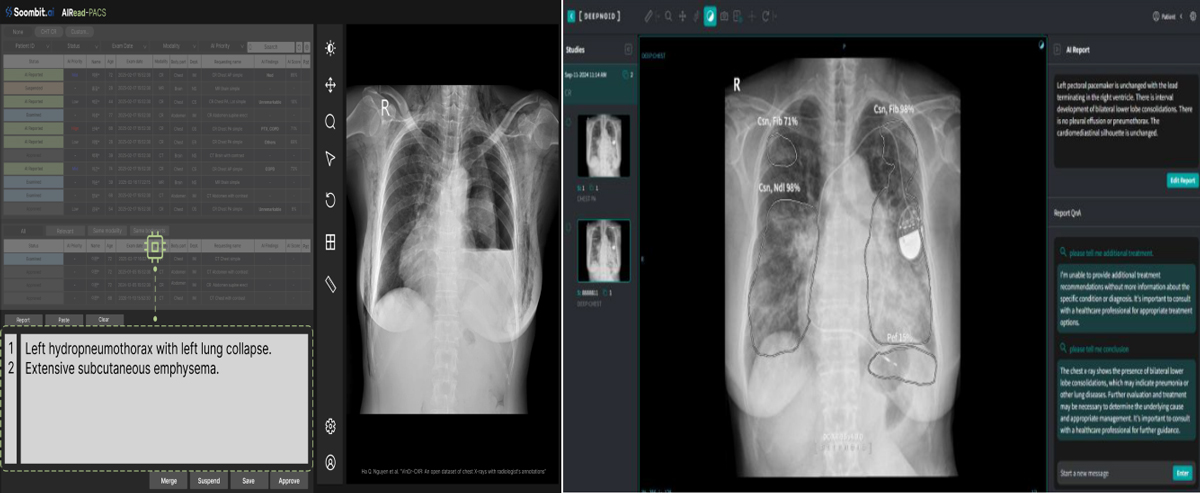

딥노이드는 지난해 11월 자사 M4CXR 임상시험을 마치고 식약처 품목 허가 결정을 기다리고 있다. M4CXR은 비전 트랜스포머와 거대언어모델 기술을 결합해 이미지와 텍스트를 동시에 분석하며 1000만 건 이상의 판독 소견서 데이터를 학습해 41종의 병변과 80개 이상의 질환을 분석한다. 부산대학교병원 연구팀 성능 평가 결과 M4CXR의 임상적으로 유의미한 소견 정확도는 85%로 나타났다. 특히 응급실 환경에서도 87.6%의 정확도를 보였으며 판독 소견서 초안 작성에는 평균 3.4초가 소요됐다. 딥노이드 측은 상반기 내 정식 출시를 목표하고 있다.

숨빗AI AIRead-CXR 역시 식약처 품목 허가 마지막 단계에 진입했다. AIRead-CXR은 흉부 엑스레이에서 감지되는 다양한 소견을 기반으로 개인 맞춤형 초안 판독문을 생성하는 소프트웨어다. 의사의 주관적 판단 개입을 배제하기 위해 흉부 영상만을 입력값으로 사용하며 외부 모델이 아닌 자체 개발 AI 모델을 기반으로 일관된 결과물을 도출하는 것이 강점이다.

자체 연구 결과에 따르면 AIRead-CXR을 활용한 영상의학과 의사는 판독 소요 시간이 평균 42% 단축되고 판독 품질은 6% 향상된 것으로 나타났다. 숨빗AI 관계자는 "현재 식약처 심사는 마지막 단계에 있으며 오는 4월 정식 출시를 목표로 의료진이 더 정확하고 신속하게 판독할 수 있는 환경을 구축해 현장의 여러 문제점을 해결하는 데 집중하고 있다"고 설명했다.